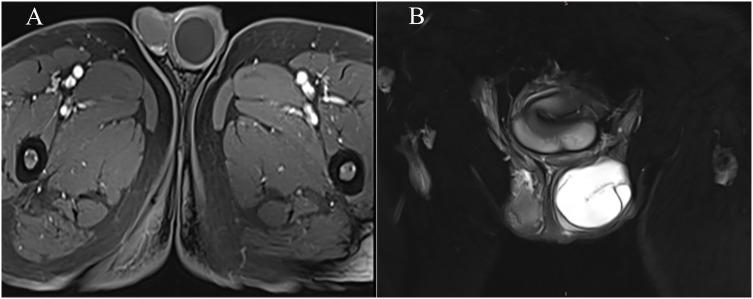

Testicular mucinous cystadenoma is a rare benign testicular tumor with the characteristics of being potentially malignant and showing atypical clinical symptoms; this article reports a case of a primary testicular mucinous cystadenoma misdiagnosed as testicular teratoma by ultrasound. A 69-year-old man was admitted to the hospital because of a 1-year history of left-sided testicular enlargement with scrotal swelling and no obvious abnormalities on laboratory tests. Ultrasound examination revealed solid-mass lesions in the left testicle, suggesting a high probability of teratoma, and contrast-enhanced magnetic resonance imaging (MRI) examination suggested an increased possibility of epidermoid cysts. Contrast-enhanced computed tomography (CT) and contrast-enhanced MRI of the preoperative abdomen and pelvis showed no other primary adenocarcinoma. Doctors performed radical resection of the left testicle. The postoperative pathological diagnosis was mucinous cystadenoma, and calcification as well as partially mildly atypical epithelial cells were discovered. Furthermore, there were no neoplastic lesions in the epididymis or spermatic cord. No metastatic lesions were found after 6 months postoperative follow-up, and the patient's prognosis remains good.

睾丸黏液性囊腺瘤是一种罕见的良性睾丸肿瘤,具有潜在恶性且临床症状不典型的特点;本文报道1例原发性睾丸黏液性囊腺瘤经超声误诊为睾丸畸胎瘤的病例。一名69岁男性因左侧睾丸肿大伴阴囊坠胀1年入院,实验室检查无明显异常。超声检查显示左侧睾丸实性肿块病变,提示畸胎瘤可能性大,增强磁共振成像(MRI)检查提示表皮样囊肿可能性增加。术前腹部及盆腔增强计算机断层扫描(CT)和增强MRI显示无其他原发性腺癌。医生对左侧睾丸进行了根治性切除。术后病理诊断为黏液性囊腺瘤,发现钙化及部分轻度非典型上皮细胞。此外,附睾及精索未见肿瘤性病变。术后6个月随访未发现转移病灶,患者预后良好。